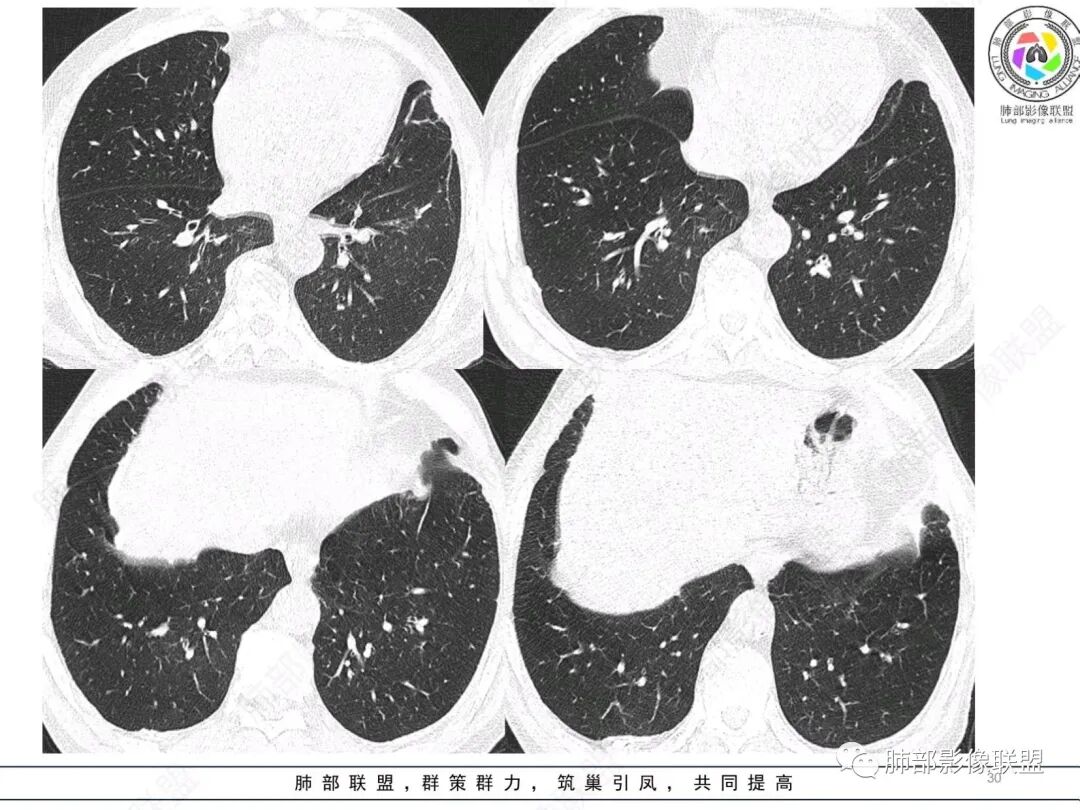

左肺上叶大肿块,膨胀性生长,边界清,密度较低,见部分坏死区,强化弱,肿块见支气管充气V扩张征,分布僵直,枯树枝特点,另一个重要特点血管造影征,淋巴瘤,肿块长轴与胸膜平行,与隐球菌鉴别,隐球荚膜抗原检查,明确诊断经皮肺穿刺。另胸膜钙化(问诊既往有无患胸膜炎病史)。

左肺上叶胸膜下肿块,宽基底与胸膜相连,跨叶裂,边缘清晰膨隆,其内支气管充气,部分扩张、僵直,无明显强化,血管造影征,考虑淋巴瘤,鉴别腺癌

左肺胸膜下巨大占位,跨叶裂,宽基底与胸膜相连,胸膜钙化,平扫密度较低,强化不明显,可见内部血管显影,支气管充气征和扩张,考虑为恶性,倾向于淋巴瘤

左侧胸腔巨大肿块,跨叶生长,临近胸膜钙化,边缘模糊,可见支气管影,定位肺内,增强后轻度强化,边缘见血管影,考虑淋巴瘤,鉴别肉瘤

左肺上叶胸膜下肿块,膨胀性生长,边界清晰,密度不均部分坏死,未见强化,病灶内支气管迂曲扩张,病灶长轴与胸膜平行,胸膜下脂肪间隙存在,胸膜钙化,考虑放线菌?毛霉?鉴别淋巴瘤

支持淋巴瘤,左上肺大肿块,有分叶,边缘光整,病灶内密度不均,可见支气管扩张征,增强后可见血管影征。周围肺野清晰。

左肺上叶肿块,宽基底与胸膜相连,跨叶裂,边缘清晰膨隆,可见小分叶,其内支气管充气,部分扩张、僵直,呈枯枝征,支气管达边征,增强无明显强化,可见血管造影征,考虑恶性病变,淋巴瘤,鉴别粘液腺癌。

大肿块,边缘光滑,深分叶

近端支气管堵塞、推移为主

部分类似于脐凹征

内部支气管扩张

肺动脉推移为主,边缘部分进入

大肿块、表面光滑但深分叶,肺门侧支气管堵塞

1)部位:周围型或中央型软组织肿块,以周围型为多见,且肿瘤多位于肺上叶。如本例:该肿瘤位于左肺上叶。

2)大小及形态:由于本病恶性程度高,早期症状不明显,发现时肿块均较大。如本例病变巨大。

3)肿块边界和边缘:多较清楚,呈圆形、类圆形,且由于肿块生长速度不均匀,可见分叶,毛刺少见。有报道肿块周围毛玻璃影是多形性癌特征表现。

4)密度:肿块平扫为软组织密度,由于体积较大,内部常见大片状坏死,可出现不规则厚壁空洞或坏死内多发无壁小空洞,坏死多不均匀:坏死灶内可见如柳絮样的斑片样强化灶,坏死边缘与非坏死区分界不清本例坏死较明显,密度不均匀。

5)肿瘤强化方式:肺部恶性肿瘤强化程度与其血供丰富程度相关,血供丰富多强化明显,反之则较差。由于PSC 周边实性部分富血供及内部黏液变性、坏死,增强后肿块多数呈轻-中度边缘环形强化或不均匀小斑片状强化。国外学者对照病理发现肿瘤细胞或胶原组织增强扫描时强化,无强化的低密度区代表了黏液样变性区和出血坏死区。